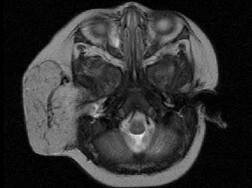

问题 老年患者,右侧面部肿胀,呈青紫色,MRI检查如图所示,请选择最可能的诊断 ( )

选项 A、神经纤维瘤 B、神经鞘瘤 C、囊肿 D、脓肿 E、血管瘤

答案 E